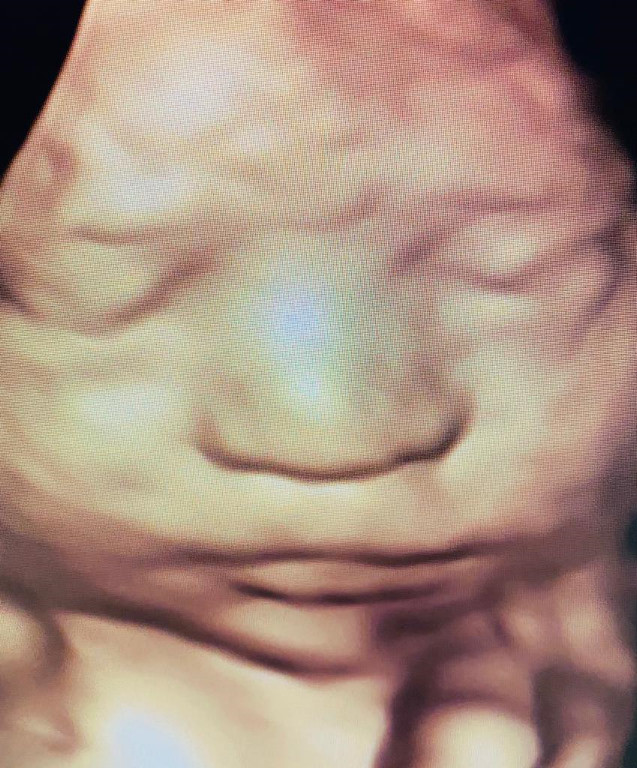

Atención de parto

Envíado por Dra. Erika Lissette Palacios